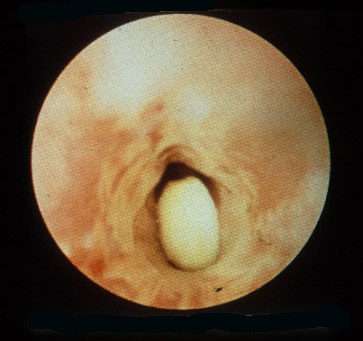

Peanut in the bronchus.